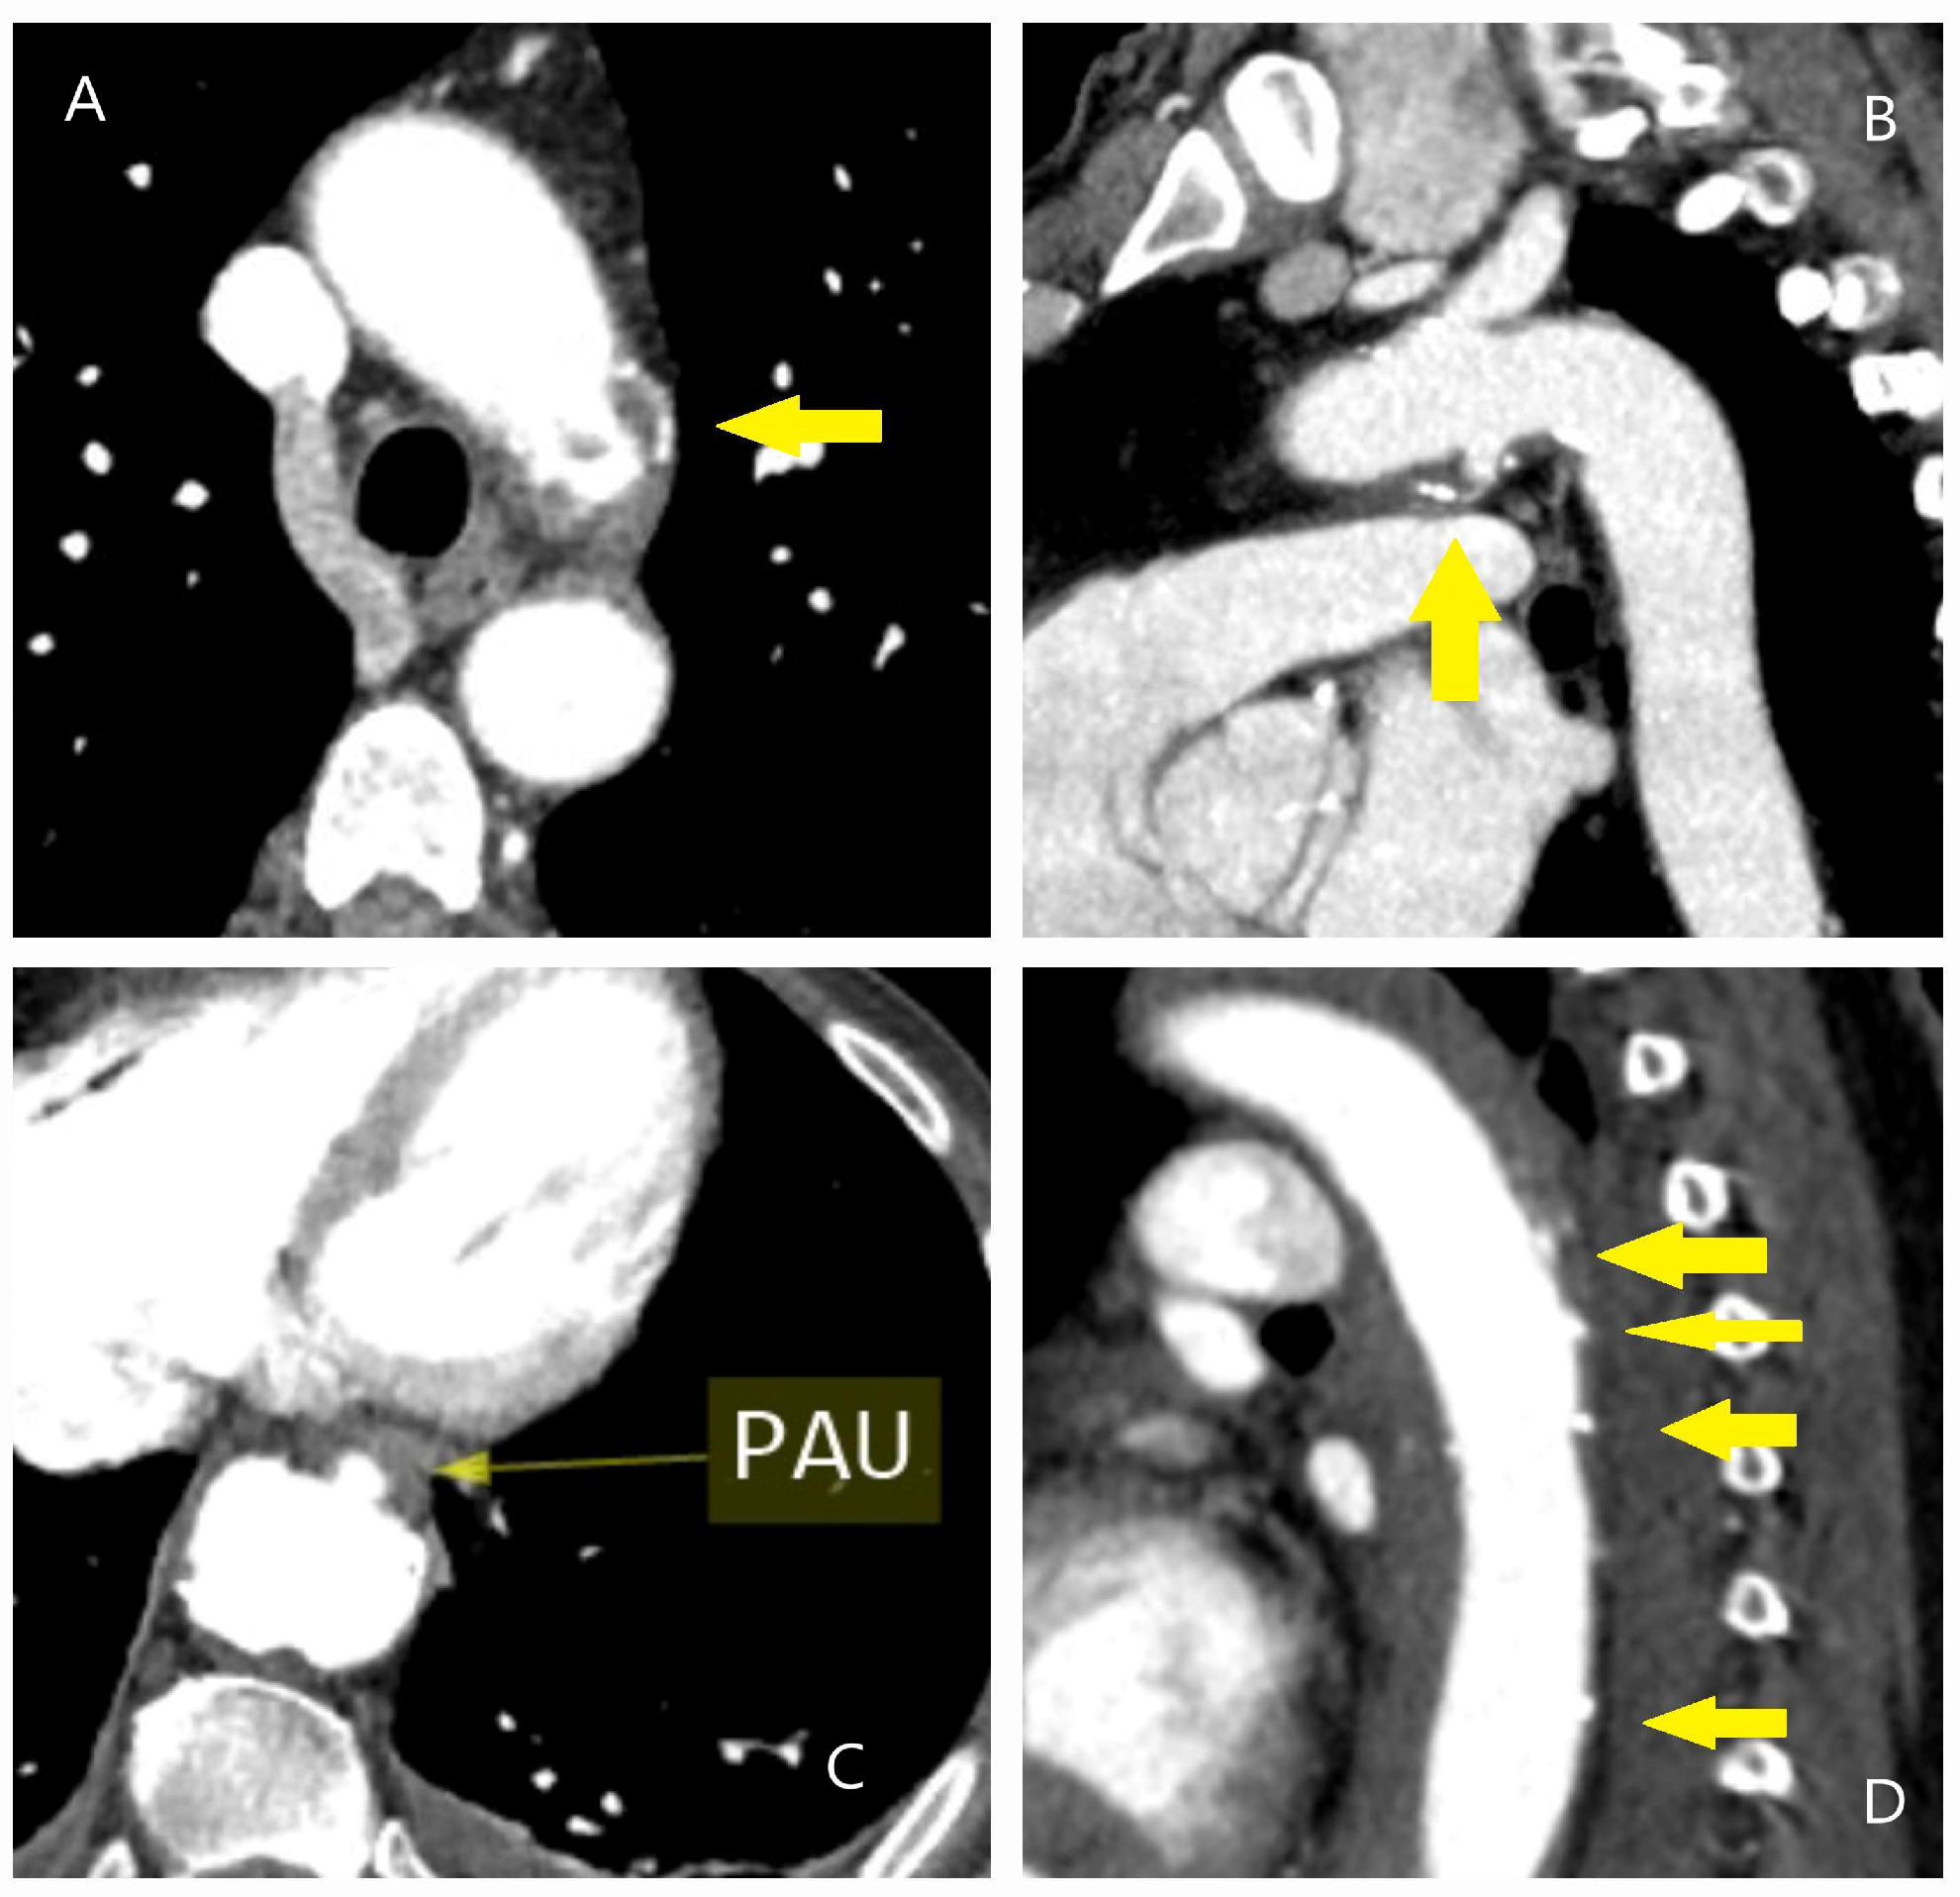

4.1. Dissection, Intramural Hematoma, and Penetrating Aortic Ulcer

5.2.3. Computed Tomography